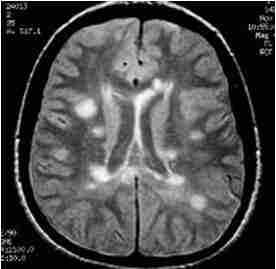

МРТ головного мозга. Рассеянный склероз. Аксиальная МРТ Т2-взвешенного типа. Перивентрикулярные очаги.

К редким агрессивным формам рассеянного склероза относится опухолевидный тип Марбурга и концентрический тип Бало. Бляшки достигают больших размеров с отеком и “слоистостью” в связи с частыми обострениями. Агрессивные варианты яркие на МРТ типа ДВИ и хорошо контрастируются.

МРТ головного мозга. Т2-взвешенная аксиальная МРТ. Рассеянный склероз, Концентрический тип Бало.